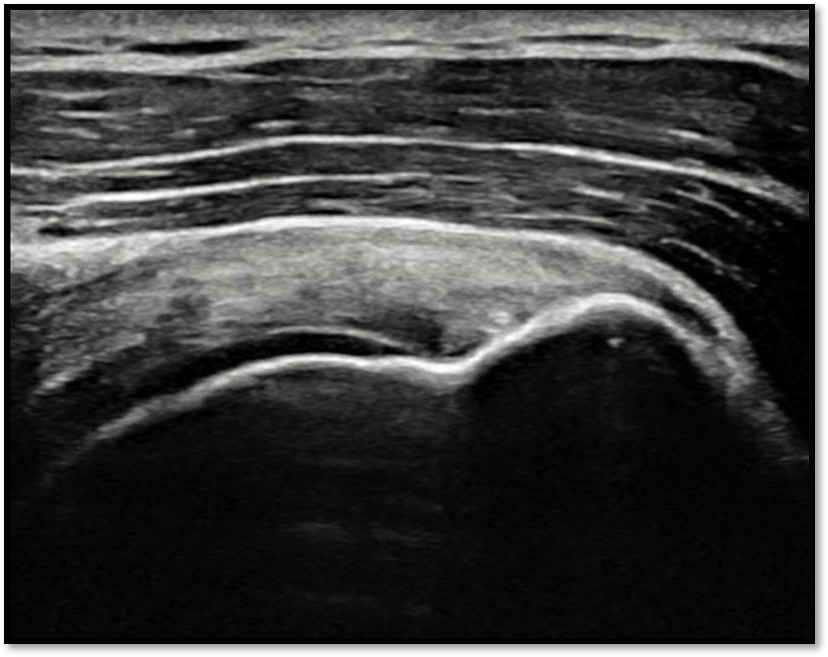

케이스 3: 소형 파열 + 젊은 환자 → 골수자극재생술

환자: 32세 남성, 크로스핏

진단:

MRI: 극상건 부분파열 (약 25%)

파열 양상: 가로 파열, 경미

치료:

골수자극재생술 (미세천공)

4세대 재생주사 병행

미세전류치료

결과:

10주 후 초음파: 파열 부위 재생 확인

4개월 후 크로스핏 복귀 (단, 강도 조절)